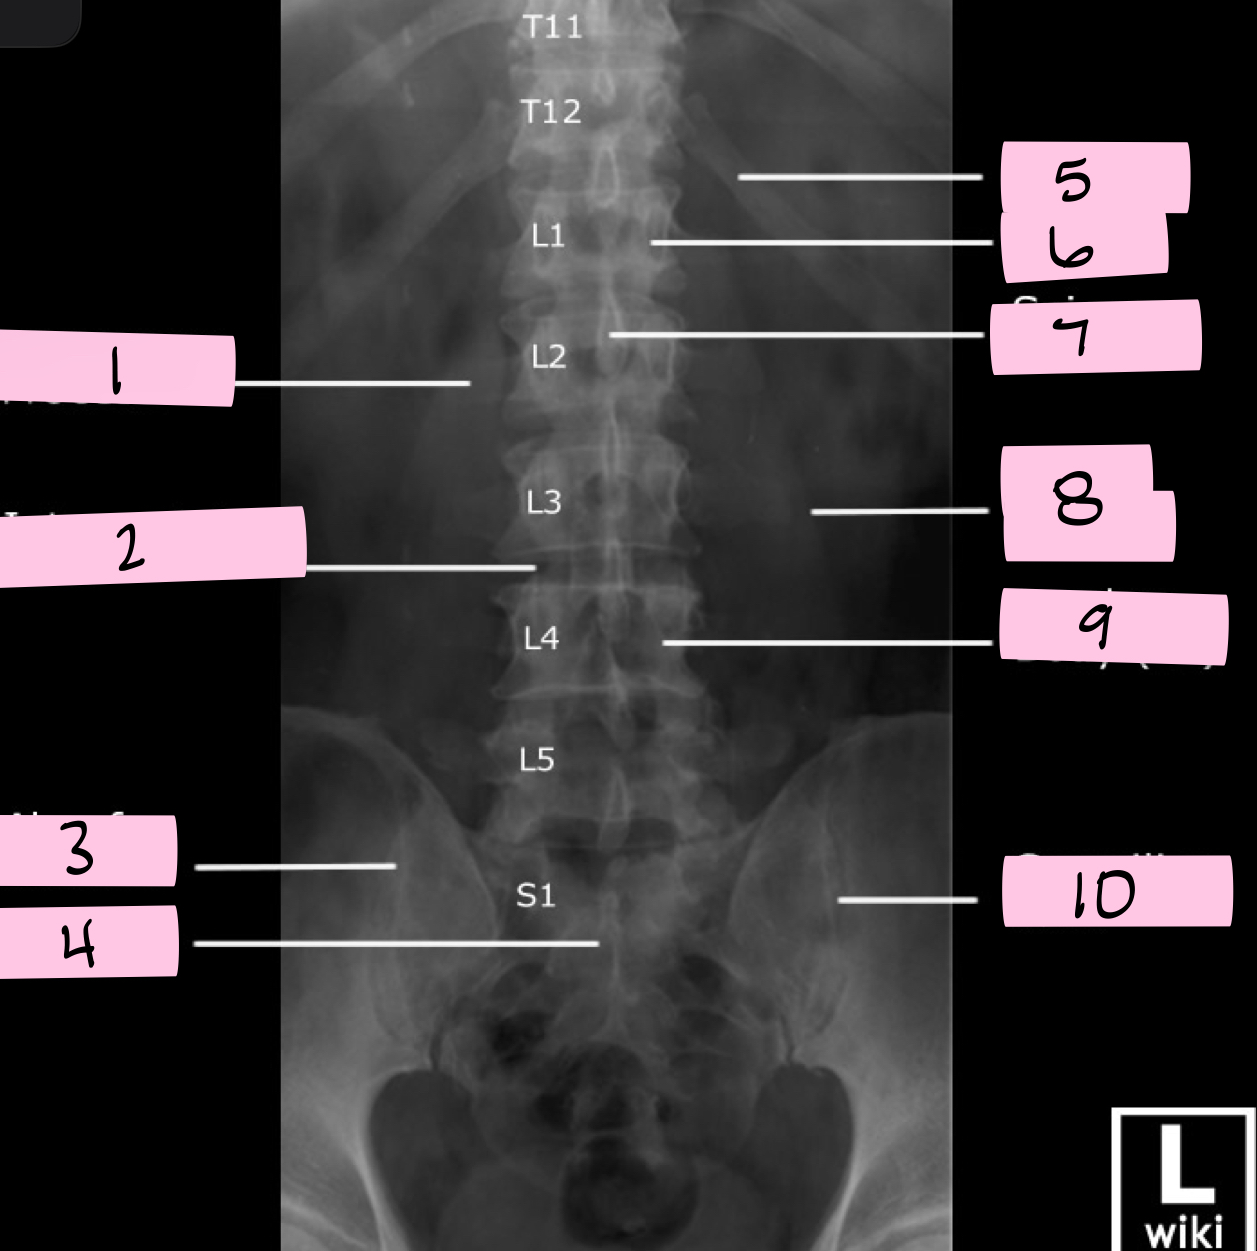

What is 1 pointing to?

Transverse process

What is 2 pointing to?

Intervertebral disk

What is 3 pointing to?

Ala of sacrum

What is 4 pointing to?

Sacrum

What is 5 pointing to?

12th Rib

What is 6 pointing to?

Pedicle

What is 7 pointing to?

Spinous process

What is 8 pointing to?

Psoas muscle

What is 9 pointing to?

Lumbar body (L4)

What is 10 pointing to?

Sacroiliac joint